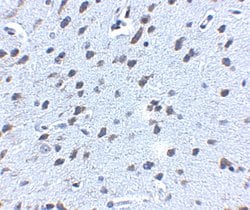

Invitrogen™ Amyloid Precursor Protein Polyclonal Antibody

Brand: Invitrogen™ PA520737

A suggested positive control is rat brain tissue lysate. PA5-20737 can be used with blocking peptide PEP-0851.

Amyloid Precursor Protein (APP) or Amyloid beta precursor protein functions as a cell surface kinesin I membrane receptor, mediating the axonal transport of beta-secretase and presenilin 1. APP is important for neurite growth, neuronal adhesion and axonogenesis. APP is a 100-140 kDa transmembrane glycoprotein that exists as several isoforms resulting from alternative splicing. Proteolytic cleavage of APP by beta- and gamma-secretases results in the generation of beta amyloid, which is the primary component of senile plaques. Senile plaques are one of the major histopathologic features of Alzheimer's disease. Abnormal regulation and processing of APP also plays a role in Down's syndrome, early onset familial Alzheimer's disease, and cerebral hemorrhage.

| Immunohistochemistry, Western Blot | |

| The immunogen is a 18 amino acid synthetic peptide within amino acids 180 - 230 of human Amyloid Precursor Protein (APP). | |

| Human, Mouse, Rat | |